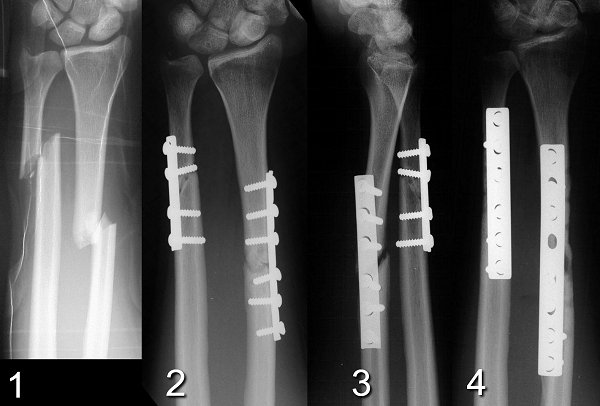

Медицинские снимки: Пластина в левом предплечье